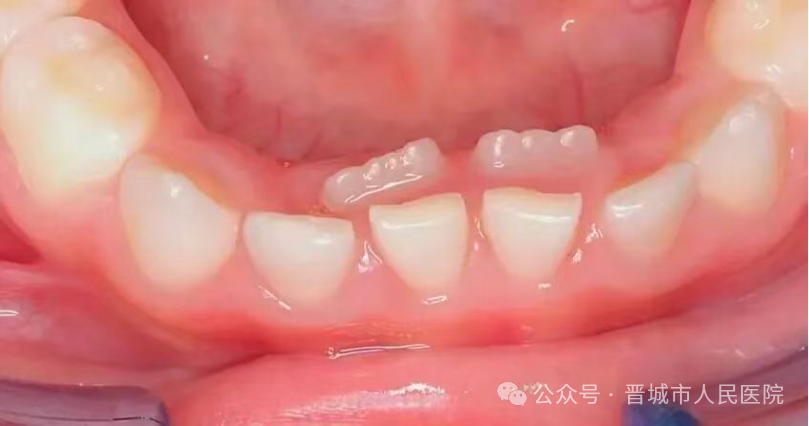

正常情况下,乳牙会按一定顺序和时间脱落,为恒牙的萌出腾出空间。乳牙滞留,即恒牙已开始萌出,但对应的乳牙仍未脱落,形成“双排牙”现象。这是儿童替牙期常见问题之一,好发于下颌前牙区域。